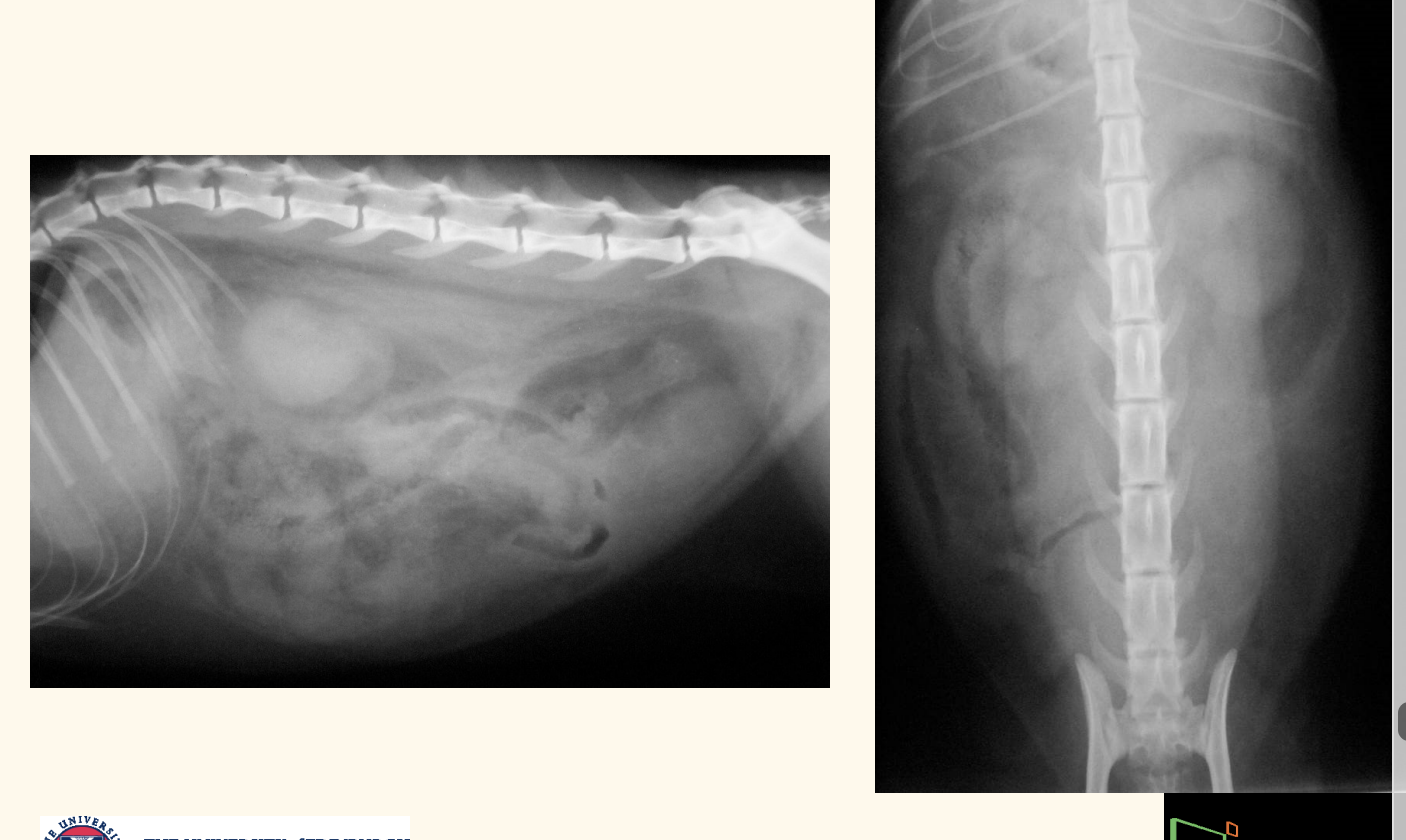

bladder rupture rx

how long?

rupture bladder: Radiography at 1 hour

Radiography at 8 hours

cannot see bladder

idelaly want to dx before 8hr

what to do for early diagnosis imaging of uroabdomen?

US